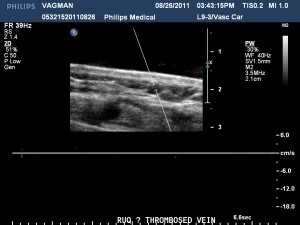

Mondor disease is usually benign. However, it has been described with local trauma, thoracic surgery, breast surgery, tight fitting clothes, infection, mammary inflammation and intravenous injection of drugs to thoracic veins. Sometimes it is associated with breast cancer and sometimes with hypercoagulability. It has been described in association with protein C deficiency, protein S deficiency and antiphospholipid antibodies. Mammography is usually un-revealing. Duplex ultrasound will show an area with no flow. There is no clear data regarding the need to explore for systemic hypercoagulability.

Mondor ultrasound

Duplex showing the cord with no flow